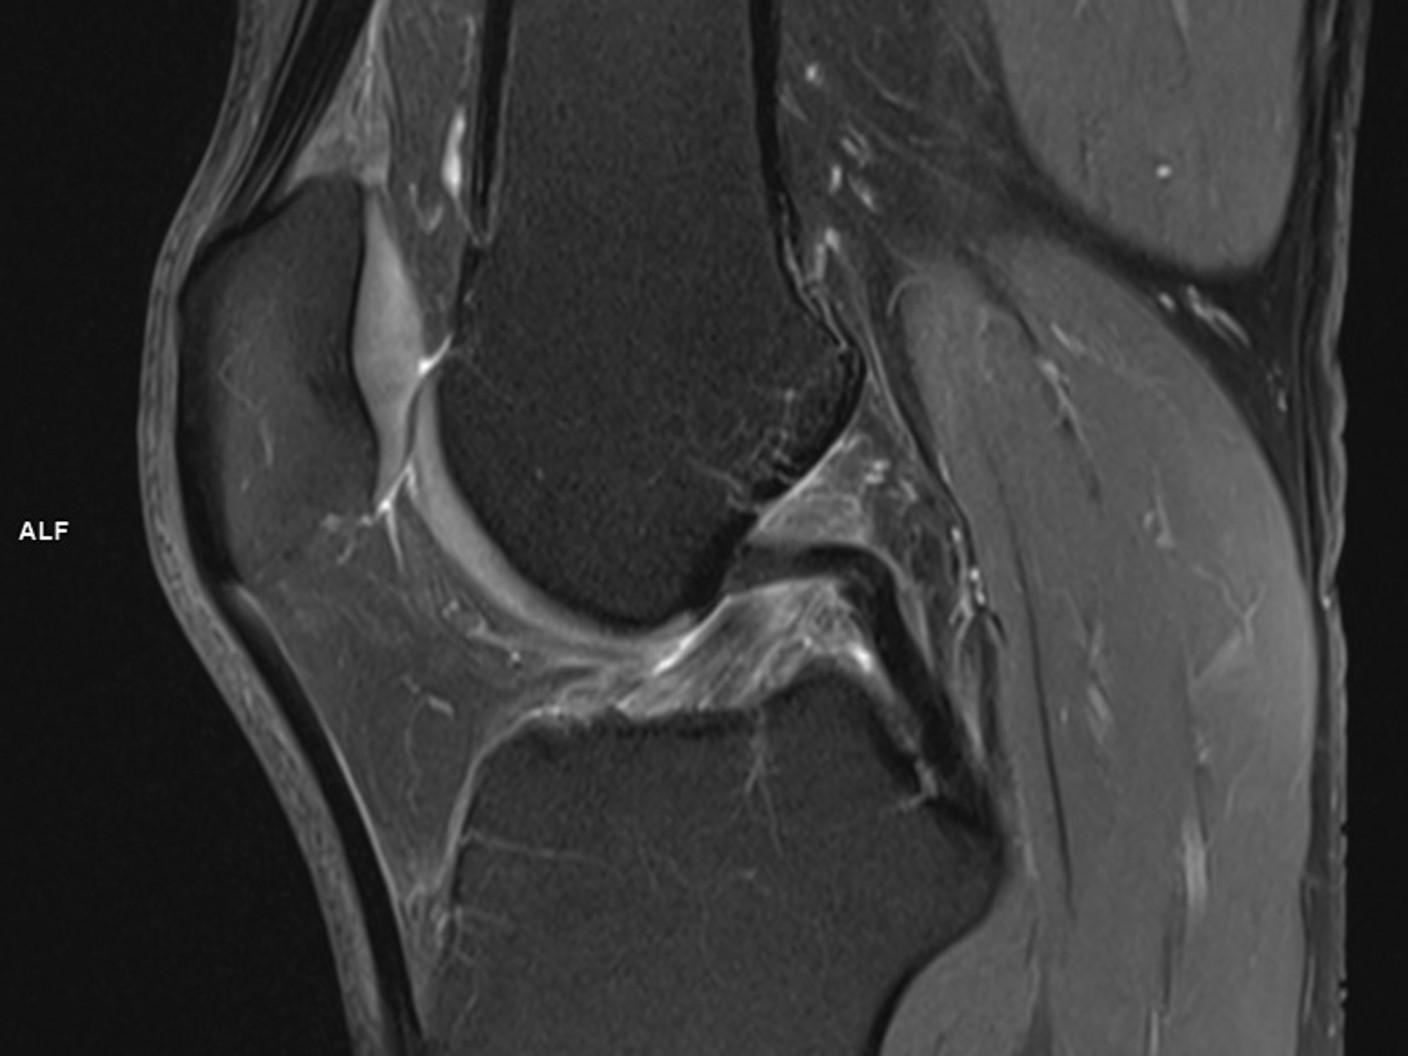

SAGITTAL PD FS TSE-MAGNETOM Vida

SAGITTAL PD FS TSE/Coil-TxRx 18CH KNEE COIL/Resolution-832/Scan Time-3:15/Aceleration-p2